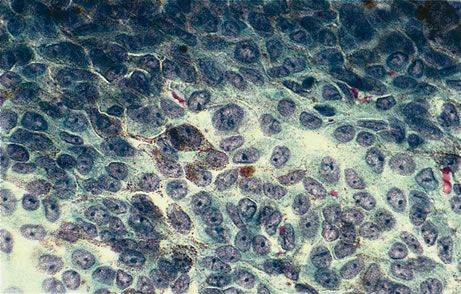

Figure 16 shows a case of what clinically and ultrasonographically appeared to be a uveal melanoma. The FNAB specimen revealed a cellular pattern that was diagnostic of a primary carcinoid (Fig. 17), and the patient responded dramatically with 40 gray of photon radiation. Figure 18 shows the FNAB cytopathology of a typical epithelioid choroidal melanoma; in contrast, a smear of a spindle cell tumor has spindle-shaped cytoplasm and smaller nuclei. Figure 19 shows a benign pigmented mass, such as a retinal pigment epithelial proliferation or a melanocytoma. In contrast to a melanoma, this type of mass has much larger pigment granules and benign cytomorphologic detail. In addition to standard cytopathologic FNAB evaluation, aspirated material may be used for several molecular biology studies (e.g., fluorescence in situ hybridization, comparative genomic hybridization), flow cytometry, special stains, tissue culture, and ultrastructural analyses.